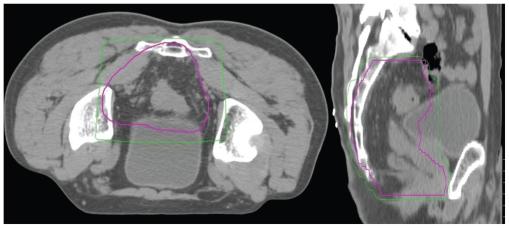

Seventeen patients with high rectal, rectosigmoid or distal sigmoid tumours above the peritoneal reflection received neoadjuvant CRT, selected on MRI findings indicating T4 disease or threatened circumferential resection margin. All patients were administered neoadjuvant chemotherapy, with Oxaliplatin or Mitomycin C and a Fluoropyrimidine. The pelvis received long-course CT-planned conformal RT, 45 Gy in 25 fractions, with a boost of 5.4-9 Gy in 3-5 fractions. Thirteen patients were treated with concomitant oral or intravenous Fluoropyrimidine chemotherapy.

Median follow-up was 37 months. Overall survival was 82.35% (95% Confidence Interval (CI) 54.7-93.9) and disease free survival 81.25% (95% CI 52.5-93.5). Only 1 patient suffered loco-regional relapse. Chemotherapy regimens were well tolerated, though some patients required dose reductions. Nine patients (52.9%) lowered pathologic disease AJCC stage, i.e. 'downstaged'. Six patients (35.3%) achieved complete pathological response. Clear margins were attained in all but 1 patient. Three patients were converted from cT4 to ypT3. No patient required a gap during CRT. One patient suffered a grade III acute toxicity, but no grade IV (RTOG). There were 3 grade III and 3 grade IV late toxicities (LENT-SOMA).

Locally advanced high rectal and recto-sigmoid tumours may be treated with pre-operative CRT with acceptable toxicity, impressive down-staging, and clear surgical margins.